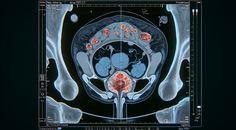

CRC Screening Strategies: Balancing Accuracy, Access, and Adherence